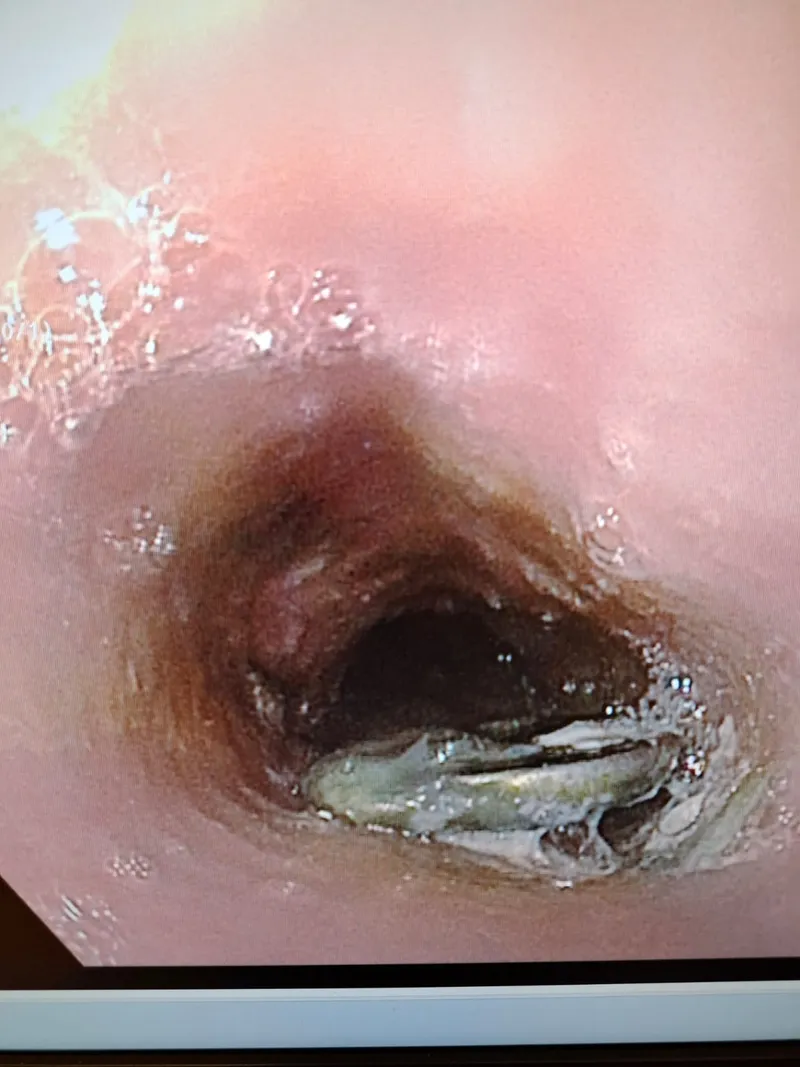

עם הגעתם למלר"ד ילדים, קיבל את פניהם ד"ר אהוד רוזנבלום. צילום חזה מהיר אישר כי הסוללה תקועה בוושט – מצב חירום רפואי מובהק. הילד הוכנס במהירות לחדר ניתוח תחת ידיו של ד"ר אייל זיפמן, מנהל שירות גסטרואנטרולוגיה ילדים. "הסוללה נמצאה נעוצה בוושט ונשלפה בשלמותה באמצעות גסטרוסקופיה", הסביר ד"ר זיפמן.

למרות המהירות, הנזק כבר החל. "למרות שעבר זמן קצר מרגע הבליעה עד להוצאת הסוללה כבר נוצר כיב בוושט", תיאר ד"ר זיפמן, אך הרגיע: "לשמחתנו בזכות התגובה המהירה של ההורים והפעולה המהירה לא נוצר נזק משמעותי יותר". הוא הדגיש כי "סוללה בוושט היא מצב חירום. מדובר באזור רגיש, שבו סוללות עלולות לגרום לנזק לרירית בתוך זמן קצר".